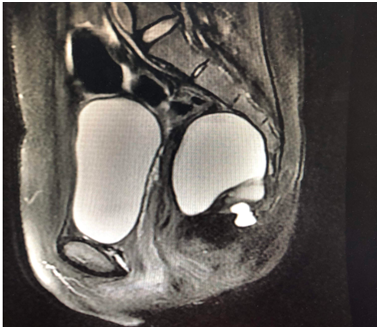

2. 肛瘘/肛周脓肿MRI导航下保留括约肌手术

MRI精准导航:术前通过高分辨率MRI三维重建明确瘘管走行及内口位置,避免术中盲目探查,精准导航